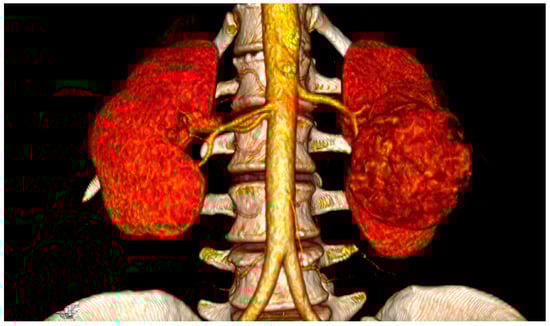

2.4. Spatial Relationships

3.2. Risk Factors

3.3. Pathogenesis, Prevention and Diagnosis

- Porpiglia, F.; Amparore, D.; Checcucci, E.; Autorino, R.; Manfredi, M.; Iannizzi, G.; Fiori, C.; for ESUT Research Group. Current Use of Three-dimensional Model Technology in Urology: A Road Map for Personalised Surgical Planning. Eur. Urol. Focus. 2018, 4, 652–656. [Google Scholar] [CrossRef]

- Lin, W.C.; Chang, C.H.; Chang, Y.H.; Lin, C.H. Three-dimensional Reconstruction of Renal Vascular Tumor Anatomy to facilitate accurate preoperative planning of partial nephrectomy. Biomedicine 2020, 10, 36–41. [Google Scholar] [CrossRef] [PubMed]

- Azhar, R.A. The influence of 3D renal reconstruction on surgical planning for complex renal tumors: An interactive case-based survey. Int. Braz. J. Urol. 2023, 49, 372–382. [Google Scholar] [CrossRef]